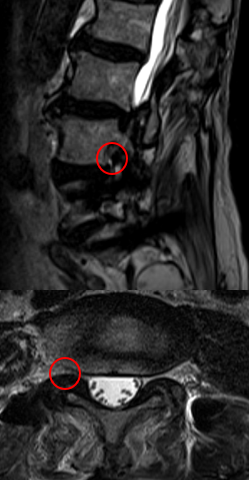

| 診察結果 | MRI画像を確認したところ、他院で手術を行ったL5/Sの除圧範囲は問題ありませんでした。しかし「右椎間孔狭窄(L4/5)」を確認し、右下肢内側の痛みと痺れは右L4神経根の症状と一致。そのためL4/5の神経圧迫が、症状の根本原因だと考えました。 また診断を進めると右下肢内側の痛みとしびれは、他院で行った後方固定除圧後の合併症である「隣接椎間障害」によるものでした。 |

| 治療内容と方針 | 右下肢内側の痛み、しびれは後方固定除圧後の合併症である隣接椎間障害によるもので、右L4/5椎間孔の狭窄症が原因だったので「PEL(脊柱管狭窄症内視鏡下術)」を実施。神経を圧迫している骨をドリルで削開しました。削開後は、椎間孔狭窄の圧迫が取れて右L4神経根が確認できました。 それと同時に、神経修復作用の効果を期待できる血小板由来の成長因子を注入する「PRP療法」を行いました。 なお、他院で手術したL5/Sの部位は再発がないので、そこの部位の治療は行っていません。 |

【術後MRI】術前にみられた狭窄部位の圧迫がとれて椎間孔が広がった所見